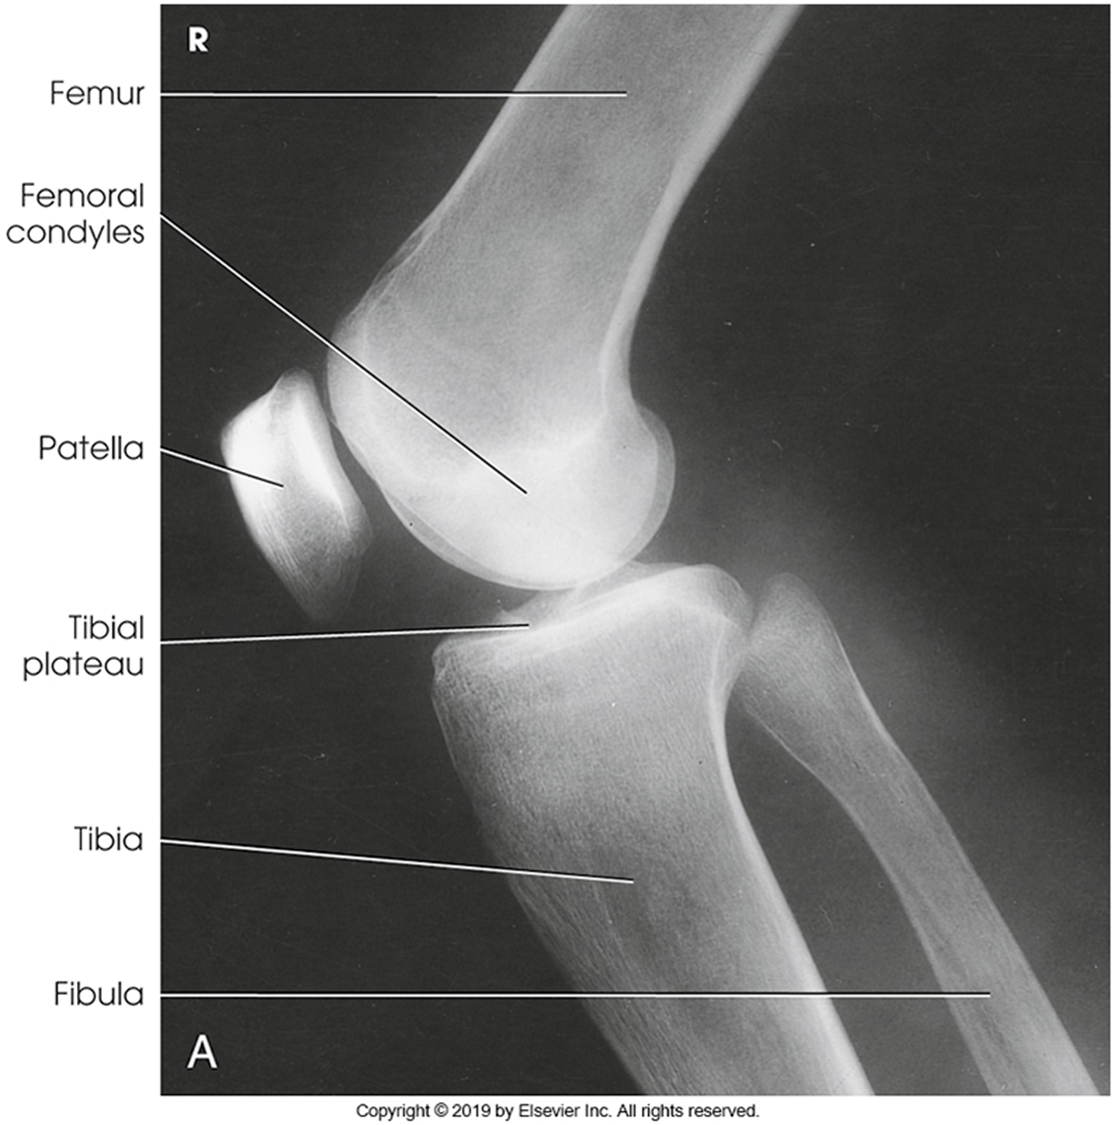

Anatomy of the knee

Trauma and Non Trauma AP Knee

•Evidence of proper collimation and the presence of a side marker placed clear of the anatomy of interest

•Knee fully extended if patient’s condition permits

•Entire knee without rotation

•Femoral condyles symmetric and tibia intercondylar eminence centered

•Slight superimposition of the fibular head if the tibia is normal

•Patella completely superimposed on the femur

•Open femorotibial joint space, with interspaces of equal width on both sides if the knee is normal

•Bony trabecular detail and surrounding soft tissues